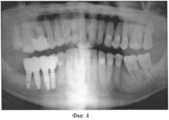

На Фиг.4 - ортопантомограмма пациента с установленными метало-керамическими протезами через 2 года.Figure 4 - orthopantomogram of a patient with installed metal-ceramic prostheses after 2 years.

Через 1 месяц после операции проведено ортопедическое лечение, которое завершилось изготовлением металлокерамического протеза. Фиг 4 - ортопантомограмма больного через 24 месяца после ортопедического лечения. На ортопантомограмме определяется стабильный уровень кости вокруг остеоинтегрированных зубных имплантатов. Окклюзия зубов хорошая. Пациент жалоб не предъявляет, результатом лечения доволен. Прикус ортогнатический. Зубной протез имеет эстетический вид.1 month after the operation, orthopedic treatment was carried out, which ended with the manufacture of a ceramic-metal prosthesis. Fig 4 - orthopantomogram of the patient 24 months after orthopedic treatment. On the orthopantomogram, a stable bone level is determined around osteointegrated dental implants. Tooth occlusion is good. The patient does not show complaints, he is satisfied with the result of the treatment. Orthognathic bite. The denture has an aesthetic appearance.